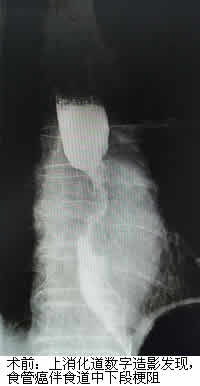

郑老伯今年已81岁高龄,因“进行性吞咽困难1月余”就诊当地医院,诊断结果为晚期食管癌。由于年纪大不宜手术,郑老伯一年内行多次放化疗后仍出现食管肿物进行性增大,原来吃面食现在只能喝水,甚是痛苦。经打听,他们了解到福建医科大学附属第一医院介入科通过一种无创的食道支架植入术可以姑息性治疗晚期食管癌,遂转诊我院。在充分了解病情及完善相关检查后,我院介入科治疗团队为郑老伯进行了这种无创手术,手术很顺利,疗效显著。术后第二天医生告诉老伯可以继续吃面食了,郑老伯非常开心,其家属也相当满意,十分感谢我院陈一平、陈仲武两位专家及其团队。

陈一平、陈仲武副主任医师介绍说,食管癌的最大问题是因食道阻塞而患者无法进食,常规上会以肠或胃造瘘的方式解决患者营养或者排便的问题。但胃造瘘仍无法让患者经口进食,而食道支架,可用以撑开肿瘤阻塞的食道,满足患者经口进食的口欲,使患者的营养得到保障,此外,该手术具有疼痛轻、并发症少等优点,对患者也是巨大的心理安慰。食道支架植入术是晚期食管癌患者实现食道再通的一种有效治疗手段。

术前胃镜+病理发现食管癌(鳞状细胞癌)